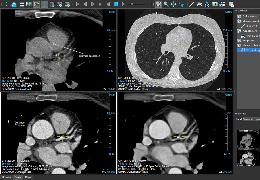

View X-Ray CT & MRI Scans Fast and Easily

Designed for surgeons, Pro Surgical 3D makes it easy to view patient scans quickly. Pro Surgical 3D facilitates the optimal 3D treatment and assessment workflows based on X-ray CT and MRI scans – and best of all, it’s FREE!

Traditional multi-planar slicing

High-quality and fast 3D reconstruction and 3D rendering

Designed mainly for CT and MR DICOM modalities.

Performs 3D reconstruction and volume rendering.

Multi-planar slicing.

Oblique slicing.

Side-by-side comparative assessment for pre- and post-operative scans.